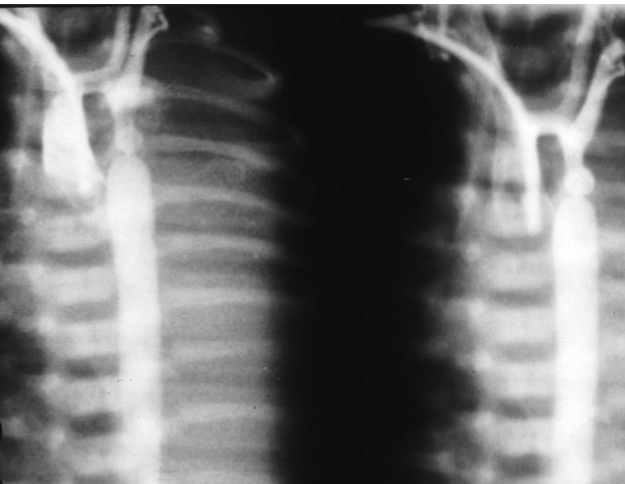

Croup

- Sign? Steeple sign.

- Diagnosis? Croup.